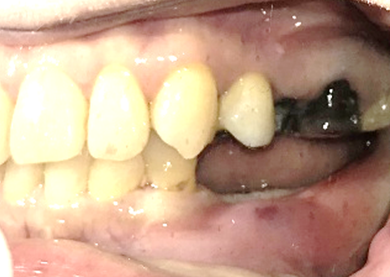

右下奥の歯が、グラグラして噛むと痛い。

治療内容

歯根の周りの骨が全く無い状態でしたので、保存することができず抜歯しました。3本歯がないところに2本インプラントを埋入しました。

所感

抜歯後、歯がなくなったところを補う方法には、部分入れ歯とインプラントがあります。この症例の場合、右下以外ほとんど歯が残っていますので、もし部分入れ歯にした場合、入れ歯のところで他のところと同じ感覚で噛むことができないので、慣れることが大変です。また部分入れ歯の支えになっている歯に負担がかかりますので、今後さらに歯を失う可能性が大きくなります。インプラントは、自分の歯と同じ感覚で噛むことができ、単独で植立していますので他の歯に負担がかかることがありませんので、更に歯を失うことを防ぎます。

インプラント2本:¥363,000✕2本=¥726,000(税込)

ポンティック1本:¥115,500(税込)

合計:¥841,500(税込)

Before

※赤丸を抜歯しました。

After